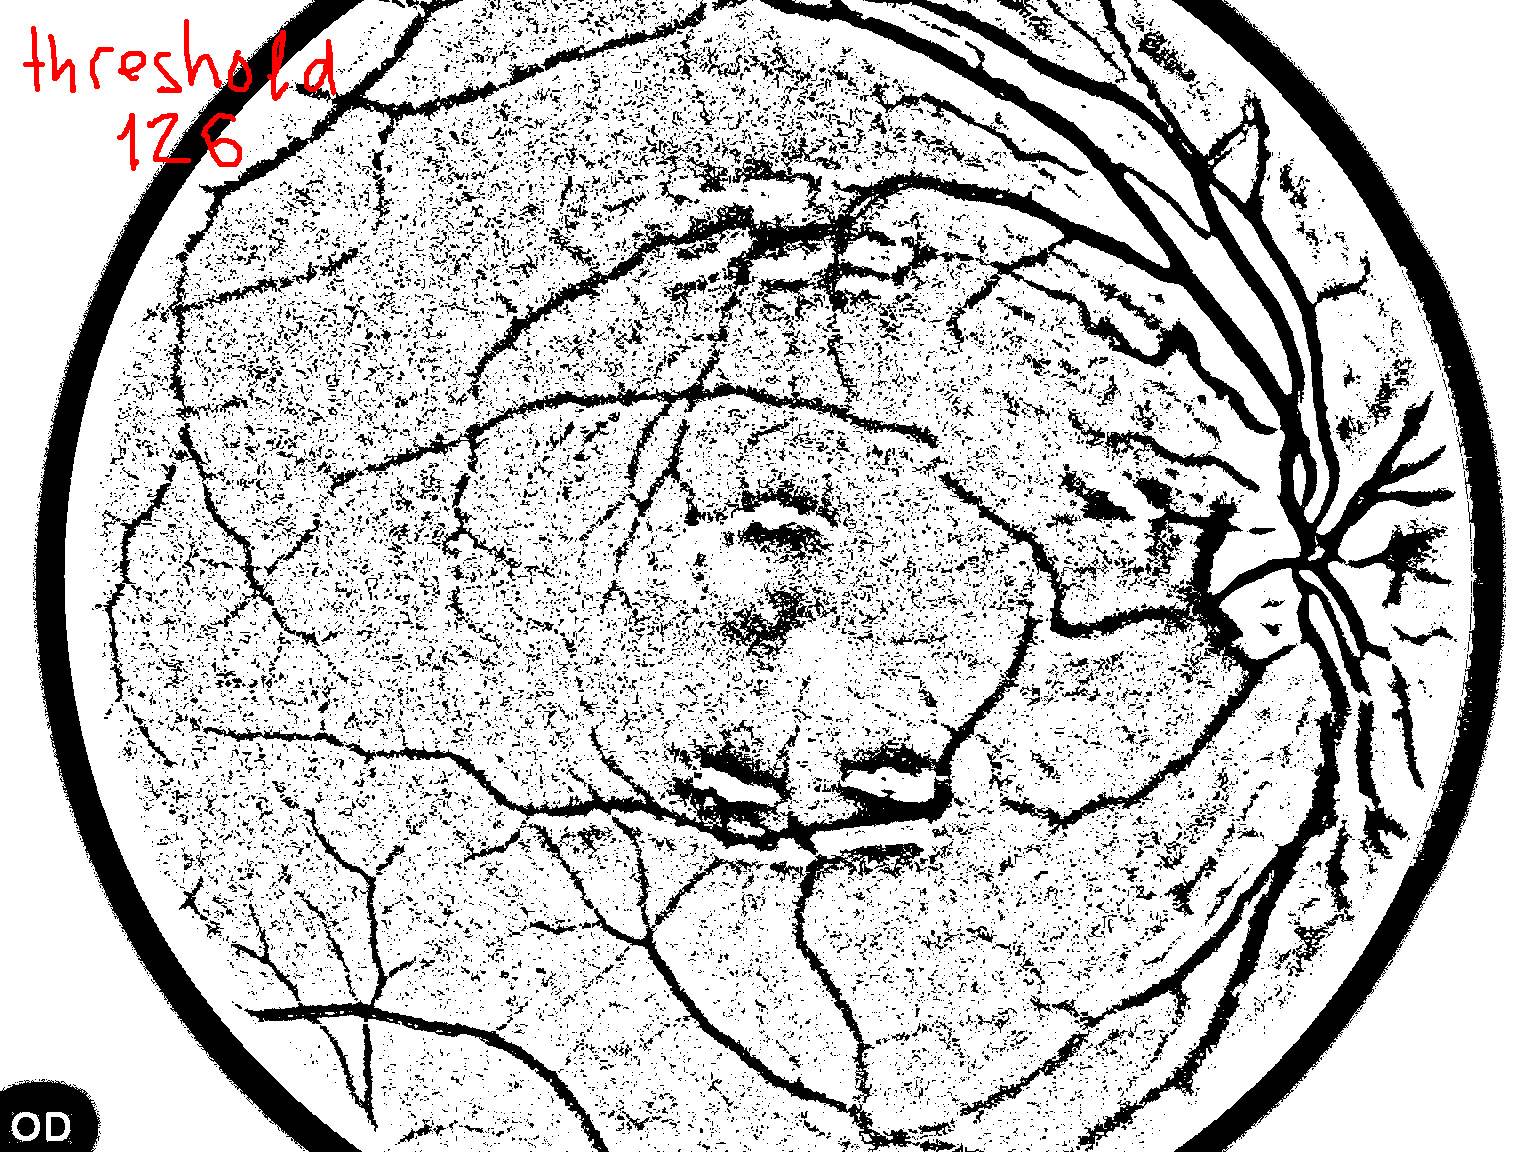

如何:高通(图像减去高斯平滑与西格玛12),然后阈值(126),然后小目标抑制(小于300个像素的对象被删除)?

(我用了你的上一张照片)